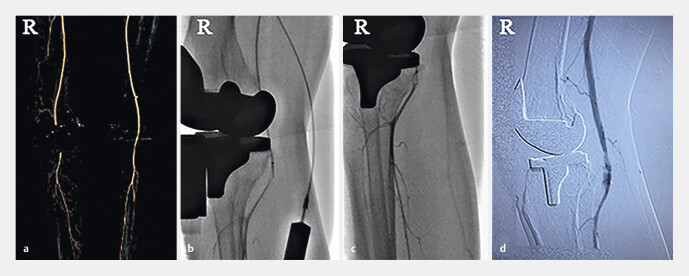

急性动脉栓塞是一个罕见的但是严重的并发症大家普遍认为,在这一情况下应立即进行再驱魔手术,但具体治疗仍未消除争议。关于两起动脉栓塞动脉血肿是动脉动脉出血引起的动手术后,两名患者右下肢体失去了知觉和行动,加上动脉器官dorsalis pedis严重恶化。心脏血管图显示大力心脏栓塞曾经有一位患者接受过内脏出血治疗,但此过程却导致右腿肌大面积感染和坏死,于是扫瞄成功后,急需经过多次肠道手术和皮肤移植。另一名患者进行了心室切除术、血管重建和预防性纤维性分裂;手术后,脚麻痹了,身体也不那么虚弱。本研究报告建议,外科医生对膝盖法老王应该给予相关的关注。手术前需要躺下并进行身体检查外科手术应该精确而小心地进行,手术后要仔细观察四肢感觉和血液循环。当脚跳不正常、动脉律动微弱时,应立即进行(多普勒超声波和动脉图谱)观察。一旦诊断出动脉血栓就必须立即恢复供血如果诊断时间延后6小时以上,预防性分泌物学可能是防止疾病发作的必要手段。

Die akute arterielle Embolie ist eine seltene, aber schwerwiegende Komplikation nach einer Knie-Totalendoprothese (Knie-TEP). Es besteht ein allgemeiner Konsens darüber, dass in dieser Situation sofort eine Revaskularisation durchgeführt werden muss, aber die spezifische Behandlung ist immer noch umstritten. Wir berichten über zwei Fälle von Embolien der Kniekehlenarterie, die durch eine akute arterielle Thrombose nach Knie-TEP verursacht wurden. Bei beiden Patienten kam es nach der Operation zu einem Gefühls- und Bewegungsverlust der rechten unteren Extremität und einer Pulsationsschwächung der Arteria dorsalis pedis; eine Angiografie zeigte eine Embolie der Arteria poplitea. Einer der Patienten erhielt eine Thrombolysetherapie, entwickelte jedoch eine großflächige Infektion und Nekrose des rechten Wadenmuskels und benötigte nach erfolgreicher Thrombolyse ein mehrfaches Debridement und Hauttransplantationen. Bei dem anderen Patienten wurde eine Thrombektomie, eine Gefäßrekonstruktion und eine prophylaktische Fasziotomie durchgeführt; nach der Operation blieben ein Taubheitsgefühl im Fuß und eine leichte Streckschwäche zurück. Die Autoren empfehlen Chirurgen, Hochrisikopatienten mit Knie-TEP eine angemessene Aufmerksamkeit zu widmen. Vor der Operation sind eine sorgfältige Anamnese und körperliche Untersuchung erforderlich. Der chirurgische Eingriff sollte präzise und schonend durchgeführt werden, nach der Operation sind das Gefühl der Gliedmaßen und die Blutzirkulation aufmerksam zu beobachten. Bei abnormalem Fußgefühl und schwacher arterieller Pulsation sollten umgehend erforderliche Untersuchungen (Doppler-Ultraschall und Arteriografie) durchgeführt werden. Wenn eine arterielle Thrombose diagnostiziert wurde, muss die Blutversorgung sofort wiederhergestellt werden. Verzögert sich die Diagnose um mehr als 6 Stunden, kann eine prophylaktische Fasziotomie erforderlich sein, um nachteilige Folgen zu vermeiden.